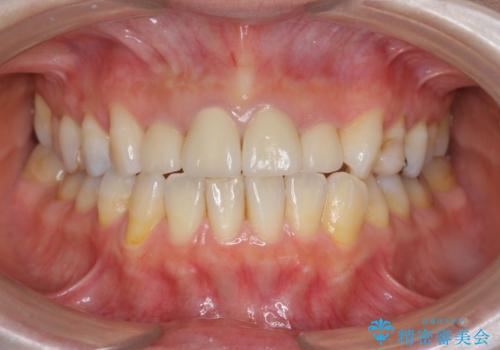

自然で美しい前歯の仕上がりとなり、大変満足していただくことができました。

- 52.8万円(ジルコニアクラウン×4・仮歯×4)費用は治療当時の料金となります